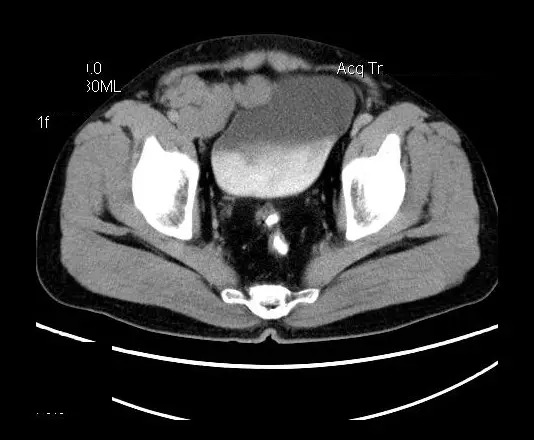

男,50岁,发现盆腔包块一月,无明显触痛,不伴发热。

【影像表现】

盆腔右前侧及邻近腹股沟区可见多发大小不等的聚集生长的结节影,病灶呈软组织密度,边缘尚规整,分界尚清,增强扫描可见不均匀强化。膀胱局部受压,盆腔未见明显肿大淋巴结影。

“盆腔”多发性神经鞘瘤